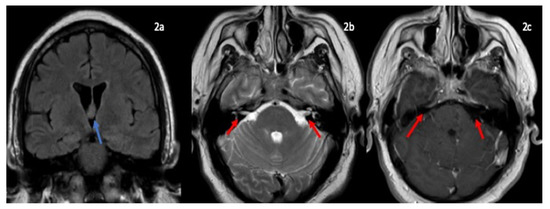

Patient followed in outpatient clinic had MRI imaging of brain showed incidental finding of colloid cyst, no facial nerve enhancement, no mass lesion, no abnormal leptomeningeal (Figure 2). Repeat MRI lumbar spine with contrast showed thickening of cauda equina nerve roots suggestive of inflammatory demyelinating neuropathy.

Figure 2.

MRI brain coronal FLAIR (2a) showing colloid cyst in the foramen of monro (blue arrow). Axial T2-weighted (2b) axial T1 post contrast images (2c) showing cranial nerve VII and VIII nerve complex (2b) and no abnormal enhancment (2c) (red arrow).